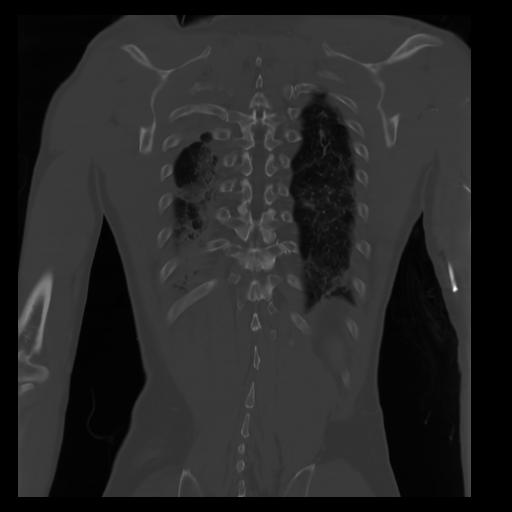

29 CUERPO,CE,Coronal,3.000,CUERPO,Coronal,